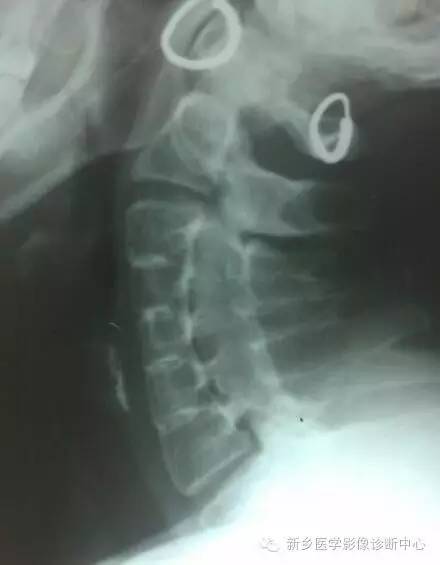

Klippel-Feil综合征就是由于基因突变或者其它因素作用下,引起的分节与再分节障碍所导致,一般分为 3种类型:Ⅰ型,为多个颈椎椎体融合;Ⅱ型,为仅1~2个椎间隙相邻的椎体发生融合;Ⅲ型,为颈椎融合同时合并胸段或腰段椎体的融合畸形。